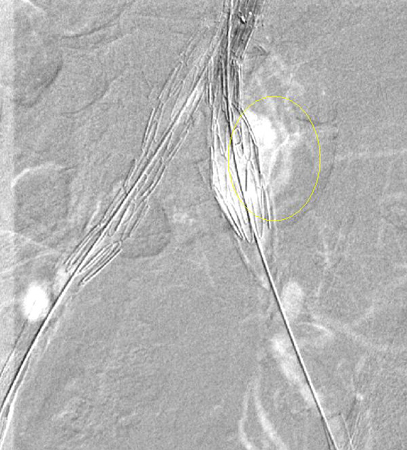

Type I endoleak at the distal left iliac anastomosis (leak encircled)

University of Michigan, specifically the cases of Dr Upchurch reflecting the Departments of Vascular Surgery and Radiology